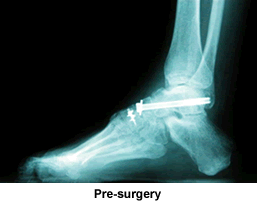

Hello, my name is Sandra Traver and I live in Millville, Pa. When I was born, I was born with dislocated hips. When I was 50 years old, I had two hips replaced, nine days apart. After the second hip replacement, I ended up with nerve damage and a drop foot on the left foot. I was told by the doctor that it could be fixed, that's when I met Doctor Kenneth Leavitt. He checked me out and found that I have Charcot Marie Tooth Disease (CMT), which is a nerve disease. He said he could have me up and walking like before surgery. He fused my foot bones together and did a nerve transplant and put a rod in my foot to be removed after 12 weeks of bed rest.